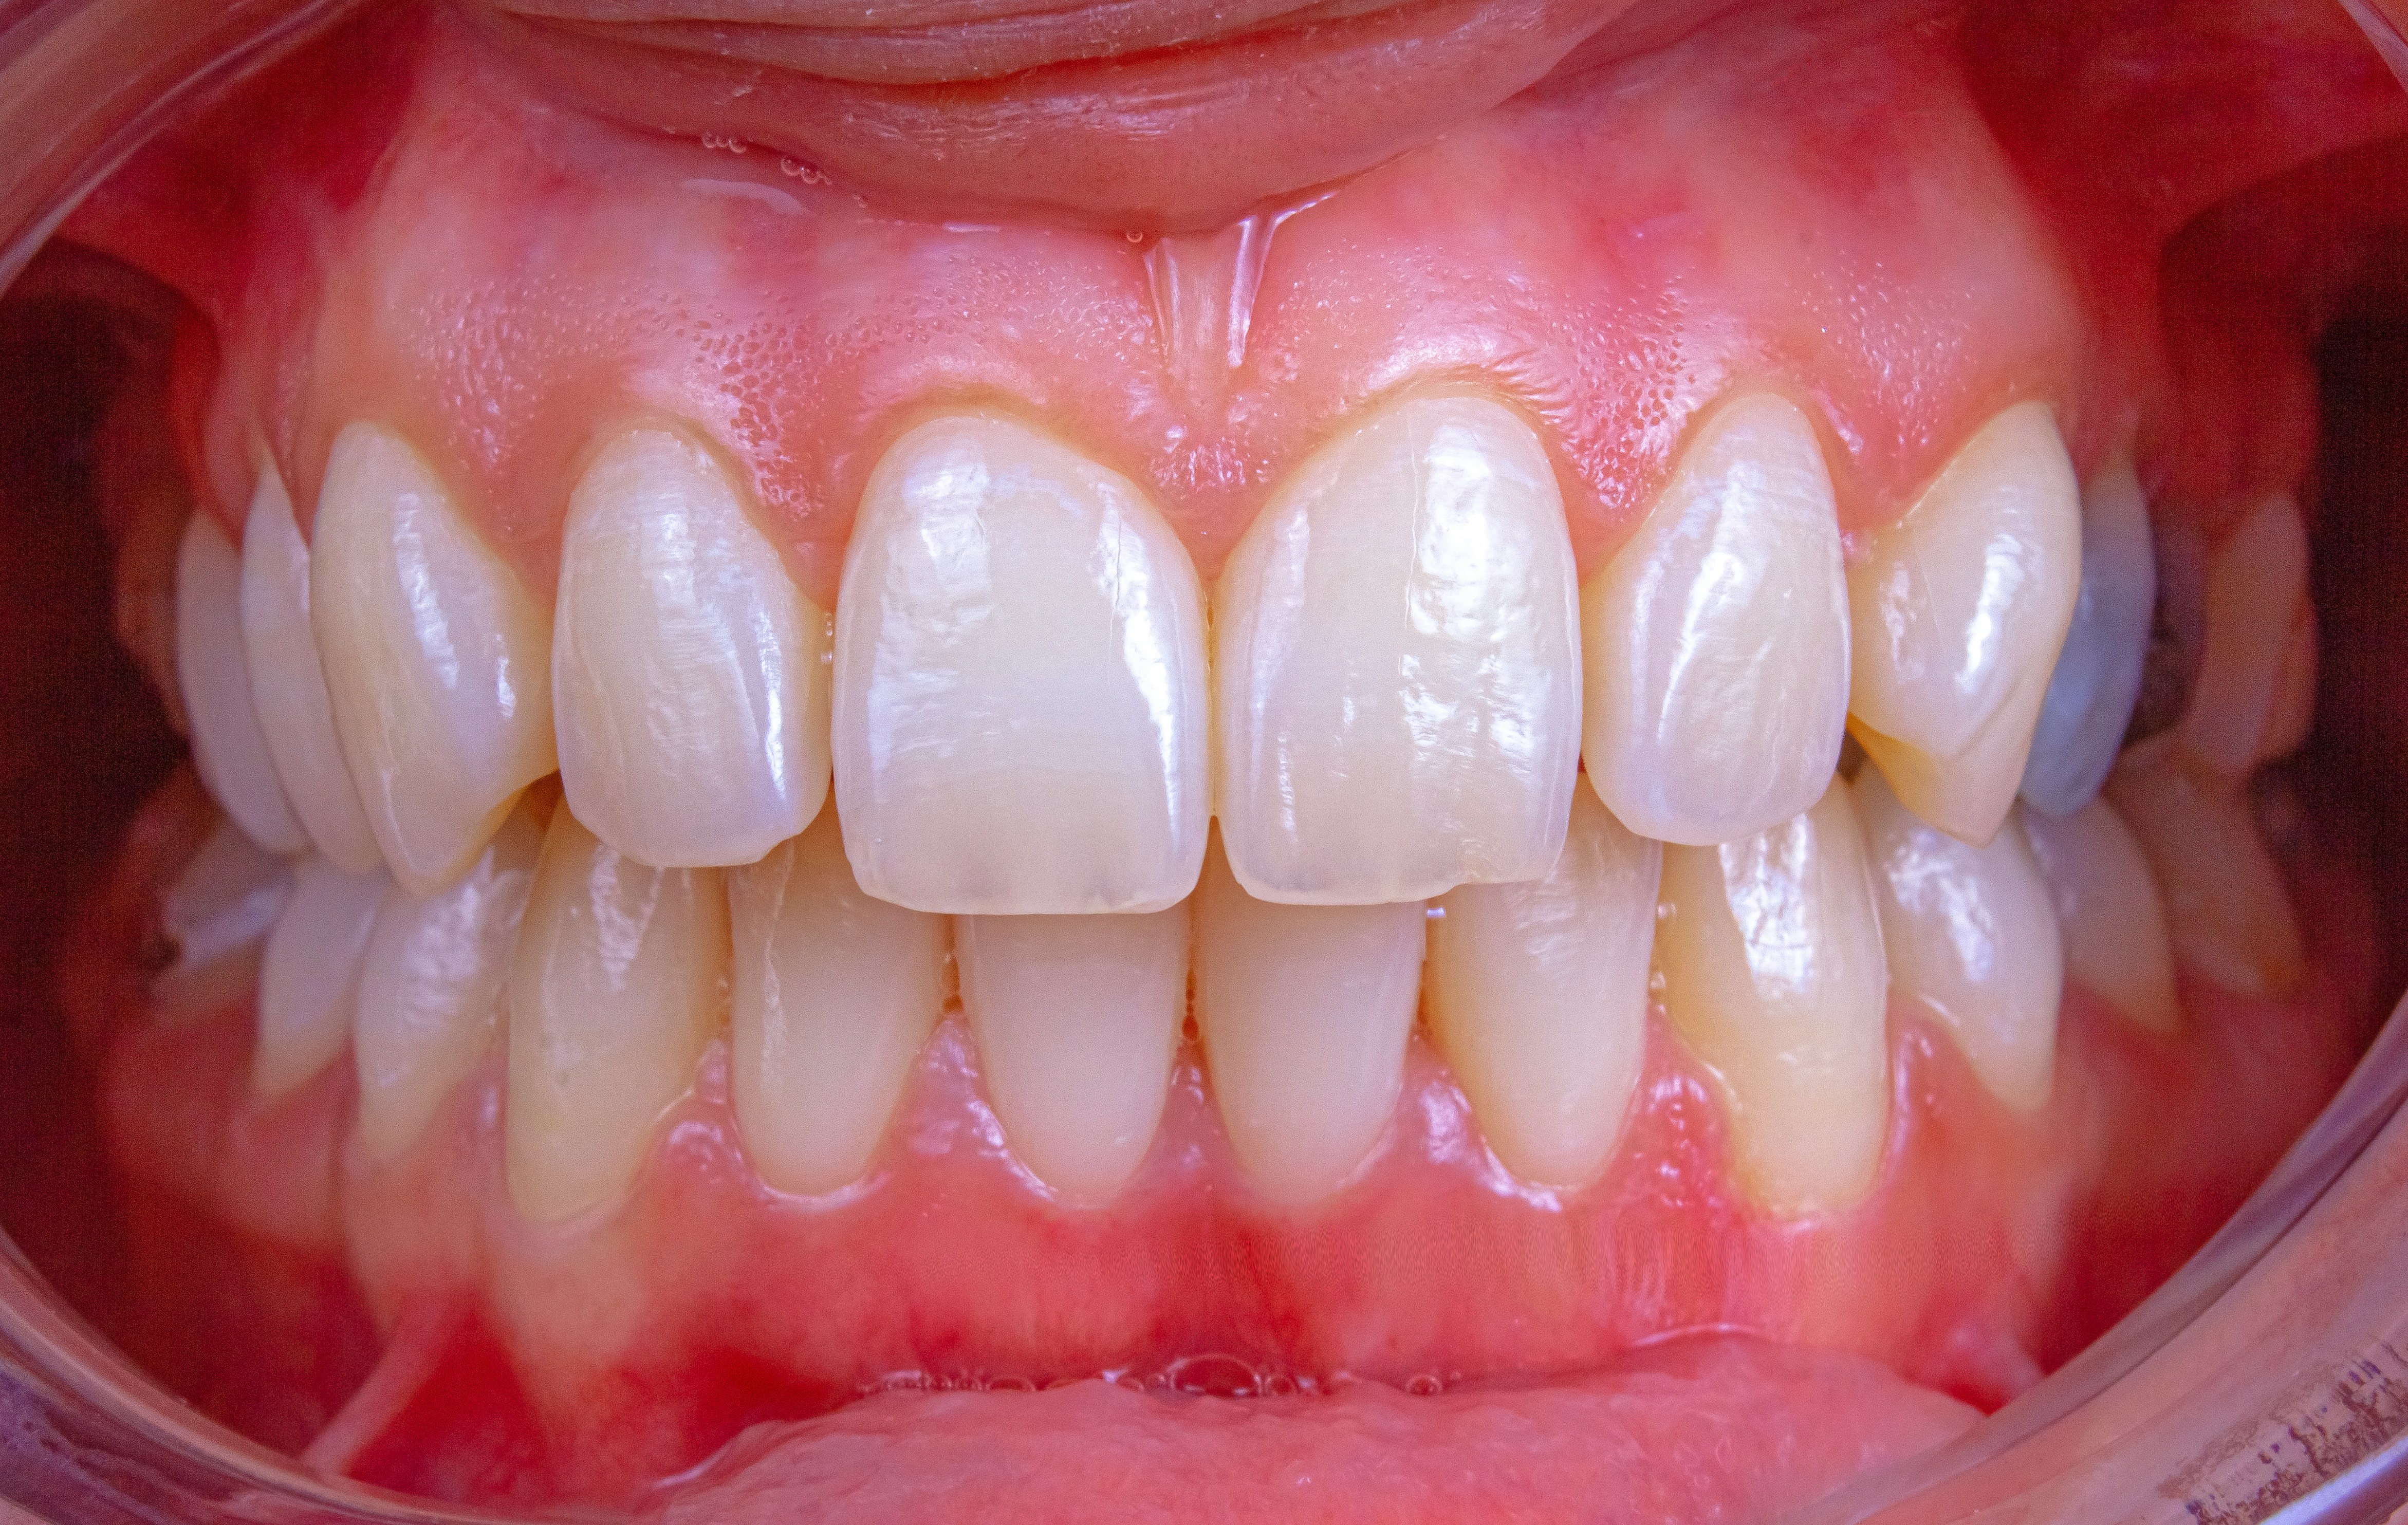

신경치료는 흔히 '치아의 신경을 빼는 치료'라고도 해요.

충치가 너무 깊게 진행되거나 외상으로 신경이 손상되었을 때 진행하게 되죠.

치아 안쪽엔 '치수(신경)'라는 조직이 있는데, 이 부분에 염증이 생기면 통증이 극심해져요.

이때 그 신경을 제거하고, 감염을 막기 위해 내부를 깨끗하게 비우고 약을 채워주는 과정이 바로 신경치료예요.